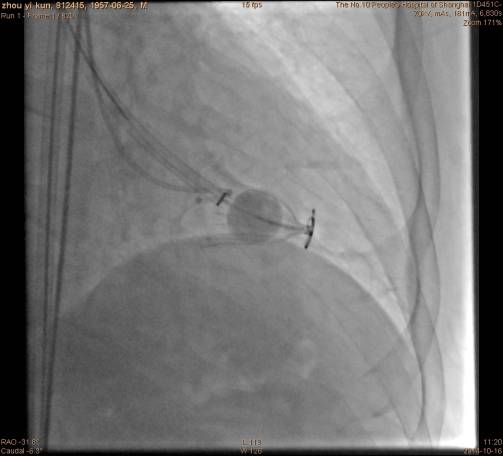

手术过程充盈球囊:

手术过程装置到位后重复左心室造影: